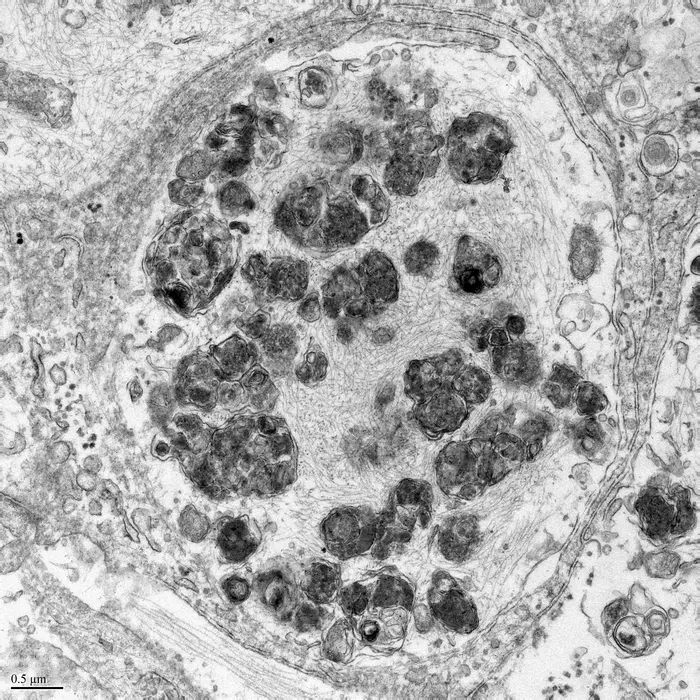

Lewy bodies are a hallmark of Parkinson's disease (PD) and other related neurological conditions. Understanding why and how they develop is critical to developing better treatments. A study from The Neuro (Montreal Neurological Institute-Hospital) of McGill University, in collaboration with its Early Drug Discovery Unit, has recreated the growth of Lewy bodies in human neurons and followed their formation to gain important insight into why and how they form. Critically, they find that immune challenge is important for this process, identifying a previously unknown link between the immune system and neurological disease.

Lewy bodies are thought to result from buildup of misfolded proteins in neurons. Previously, the only way to study them in human neurons was through brain autopsy, which is not ideal because cells break down quickly after death. In this study, neuroscientists used human stem cells to create Lewy bodies in living dopaminergic neurons, the kind of cells especially at risk in PD.

By following the development of Lewy bodies in real-time, the scientists discovered that in dopaminergic neurons, the immune response impairs autophagy—the removal of damaged cellular materials. They also found that in these cells, Lewy bodies are membrane-bound, and contain other organelles and membrane fragments, contradicting previous dogma that Lewy bodies were composed exclusively of misfolded proteins.